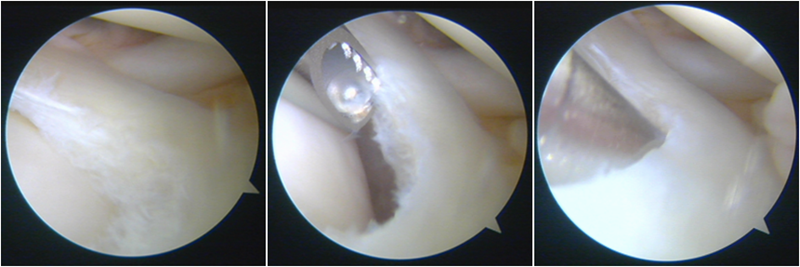

韧带导入过程

送止血带后韧带表明血管膜